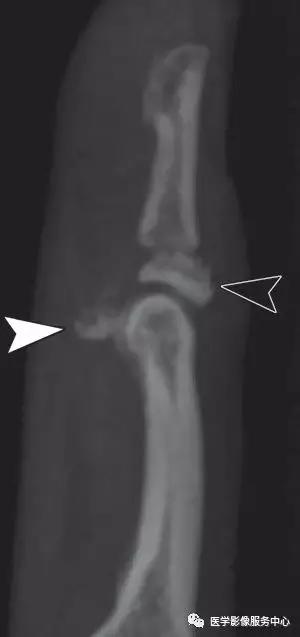

中央腱束撕脱:

伸指总肌的中央腱束的骨性撕脱,略示移位。合并轻度近端指间关节的过屈及远端指间关节的过伸,符合纽孔状畸形。